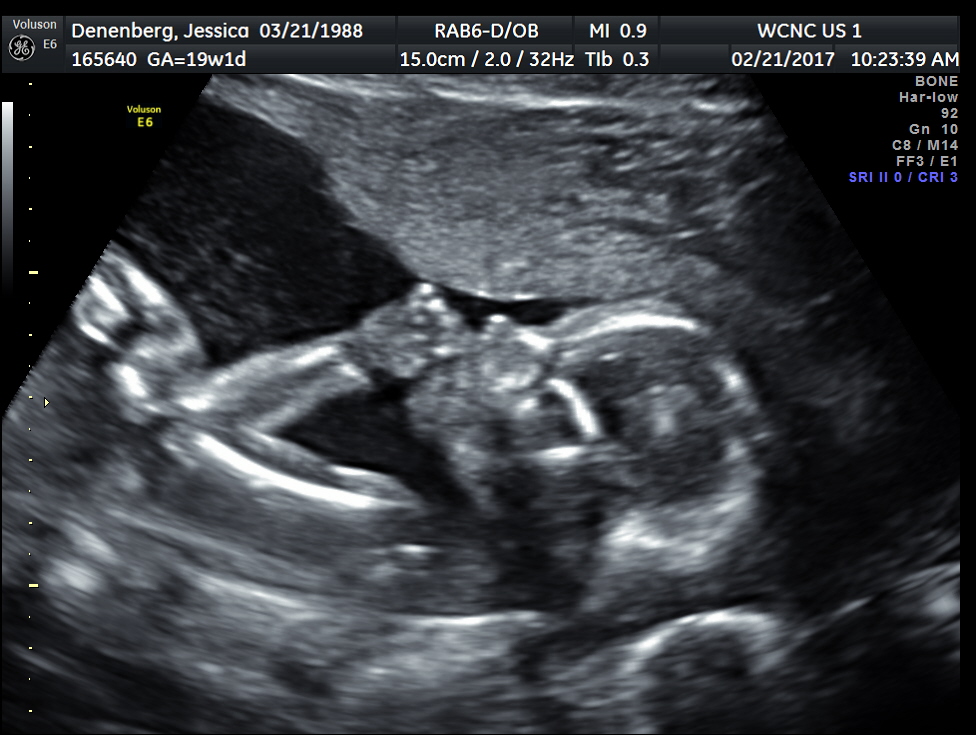

This past Tuesday, we had our first ultrasound. I didn’t really know how nervous I was for this until it was happening. There were so many “what ifs” and fears I carried with me until now. I have often read and heard and had friends experience heartbreaking losses when they get their 20 week ultrasound. We pray for those friends often.

We also praise God that we are having a healthy, fully developed, sweet baby GIRL!!!